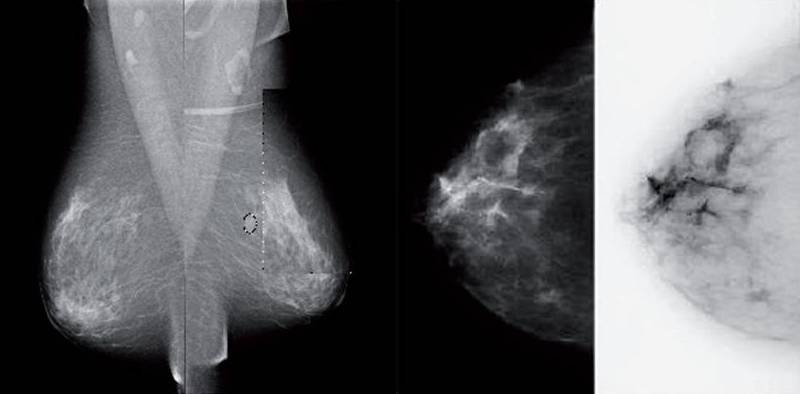

- Galaktographie (Füllung der Milchgänge mit Röntgenkontrastmittel)